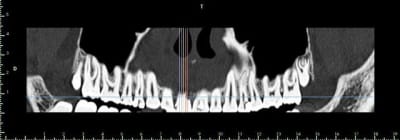

bon, autre truc plutôt défavorable au greffon ramique...je viens de vérifier: contact des apex de 38 et 48 avec le NDI...et comme les dds ont suffisamment de place...on laisse tranquillement évoluer...

sincèrement...j'ai pas trop envie de me casser la tête...

un greffon type puros ou biobank en bloc me semble être un bon compromis....

juste des particules d'os de synthèse...quid de la stabilité réelle du volume par rapport au bloc?

je sais que 17 ans c'est jeune...mais entre la greffe (bien 6 mois de cicat) la pose de l'implant (avec 3 ou 4 mois d'ostéointégration) on va vite être à 18 voir 19 ans...et là, je pense qu'on peut concevoir un ttm implantaire...non?

Sinon concernant ton cas j'ai l'impression qu'il y a de l'os en mesial et distal de ta dent du coup si c'est bien le cas je ferais de la rog avec une membrane pinsee

Growler, ton cas avec greffe en bloc allogreffe as-tu une radio post-op? la hauteur cervicale du greffon avec la perte osseuse au mésial de la 12 m'inquiète?